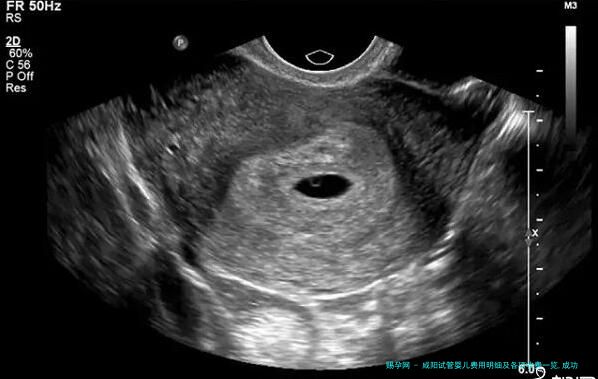

术前检查费(约3,000-8,000元):这是翻开试管在周期之前的必需步调,目的在于评价夫妻两边的身体状况,订定个性化方案。检查项目繁多,包括女性的性激素六项、AMH(抗缪勒管激素)检查、妇科B超,以及男性的精液解析等。

| 取卵手术 | 获取卵子 | B超引导下经阴道取卵,通常需 | 5,000 8,000 元 | 手术时间短,但为关键步骤 | 医保可 *** |

| 胚胎移植手术 | 将胚胎植入子宫 | 在B超引导下进行 | 3,000 5,000 元 | 手术过程无痛,时间短 | 医保可 *** |